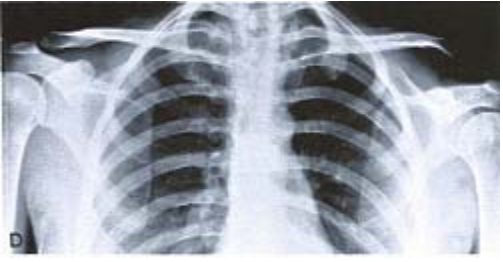

29 有關單發性肋骨骨折,下列所述何者正確?①單發性肋骨骨折通常可當作嚴重瘀血來治療 ②可發生在 直接撞擊之後 ③發生骨折時,病人感到胸部一陣突發性疼痛,而後在深呼吸時會有疼痛感 ④醫者 彈壓肋骨時會使病人感到疼痛 ⑤老年人劇咳後也易發生 (A)僅②③⑤ (B)僅①②④ (C)僅①③④⑤ (D)①②③④⑤